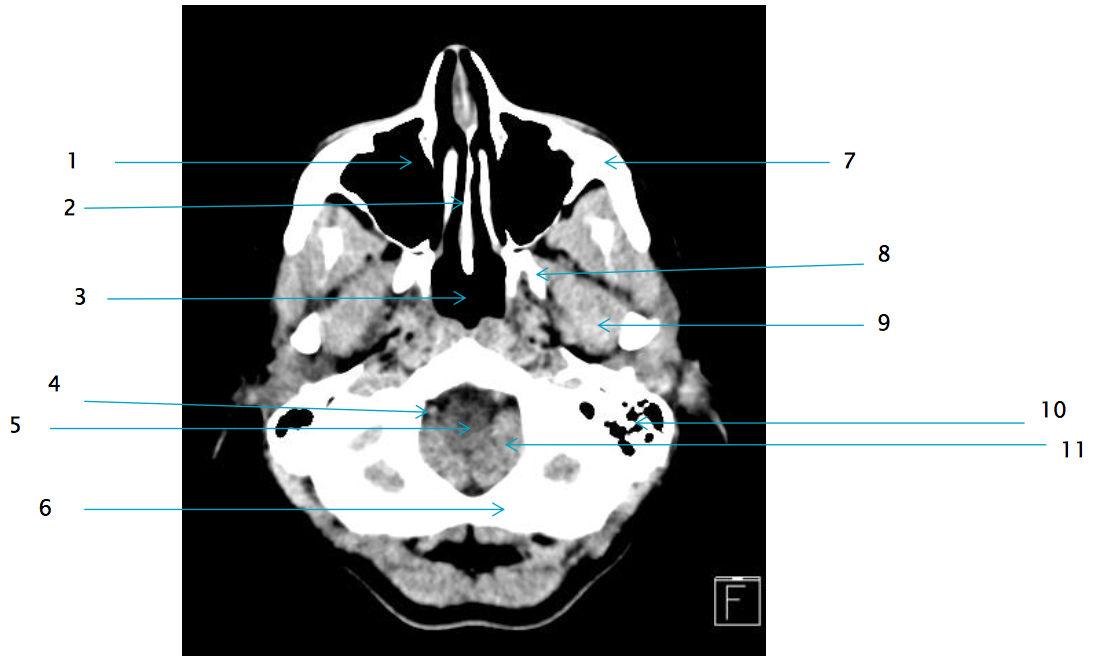

6

L occipital bone

7

L zygomatic arch

8

L lateral pterygoid plate

11

L Cerebellar tonsil

9

L lateral pterygoid muscle

1

R maxillary sinus

2

vomer

5

medulla oblongata

10

L mastoid air cells

3

4

R vertebral artery